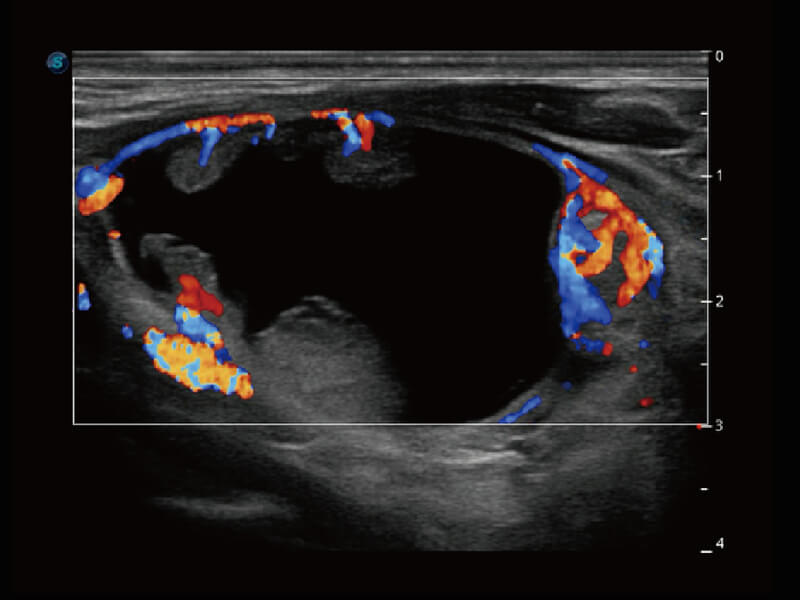

S60探头工艺,从前端信号处理每一个环节采集无损声学数据,真实还原组织原貌,再现解剖细节。